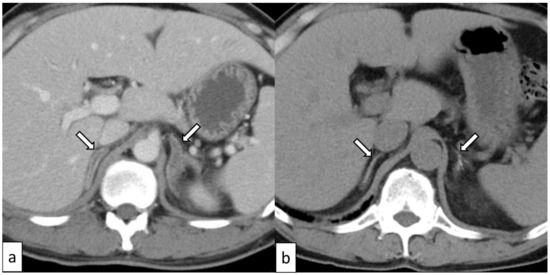

| Kano [15] | 50 (Figure 3) | Male | NO | Hemorrhage and contralateral adrenomegaly * | Bilateral | YES | YES | YES | YES |

3.5. Adrenal Hemorrhage